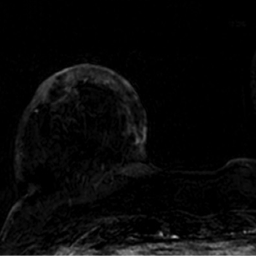

2. Describe los hallazgos por RM:

- A. Cambios en MD en relación con cuadrantectomía previa sin realces sospechosos.

- B. Cambios posquirúrgicos en MD con realce tipo no masa en región retroareolar con curvas funcionales inespecíficas (tipo 1).

- C. Engrosamiento cutáneo en CCII de MD con realce heterogéneo nodular asociado a un realce tipo no masa retroareolar con curvas funcionales sospechosas (tipo 2).

- D. Engrosamiento cutáneo y retracción de complejo areola pezón (CAP) de MD con múltiples realces nodulares retroareolares de distribución ductal con curvas funcionales inespecíficas (tipo 1).

- E. Engrosamiento cutáneo post-radioterapia en MD sin otros hallazgos sospechosos.